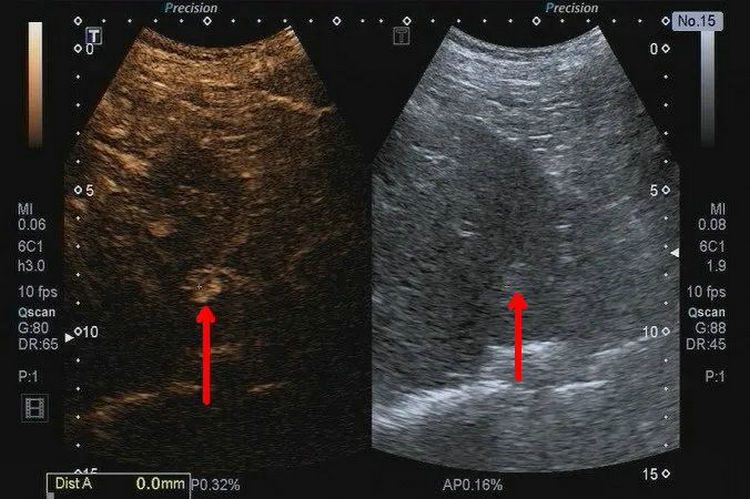

当超声体检发现肝内实性结节时,需要进行良恶性鉴别,由于普通超声提供的信息较少,此时就需要进一步的检查来确定实性结节的良恶性,检查方式主要是增强CT和超声造影。

超声造影是经静脉团注超声造影剂,通过观察结节造影模式来对结节进行良恶性的鉴别。超声造影的主要优势为:

1.实时连续性,5分钟连续实时的对结节进行扫查。

2.几乎对人体不会产生毒副作用。目前广泛应用的超声造影剂是声诺维及示卓安,主要成分是六氟化硫及全氟丁烷,均为惰性气体,15分钟后经呼吸排出,为肝肾功能不全、无法进行增强CT扫描的患者提供一种新的检查手段。

3.可重复性,由于超声检查的安全无辐射的优势及超声造影剂的安全性,使得超声造影在短期内可及进行重复检查。

4.超声造影主要是微循环灌注,在增强扫查时,微细结构显示更加清晰。